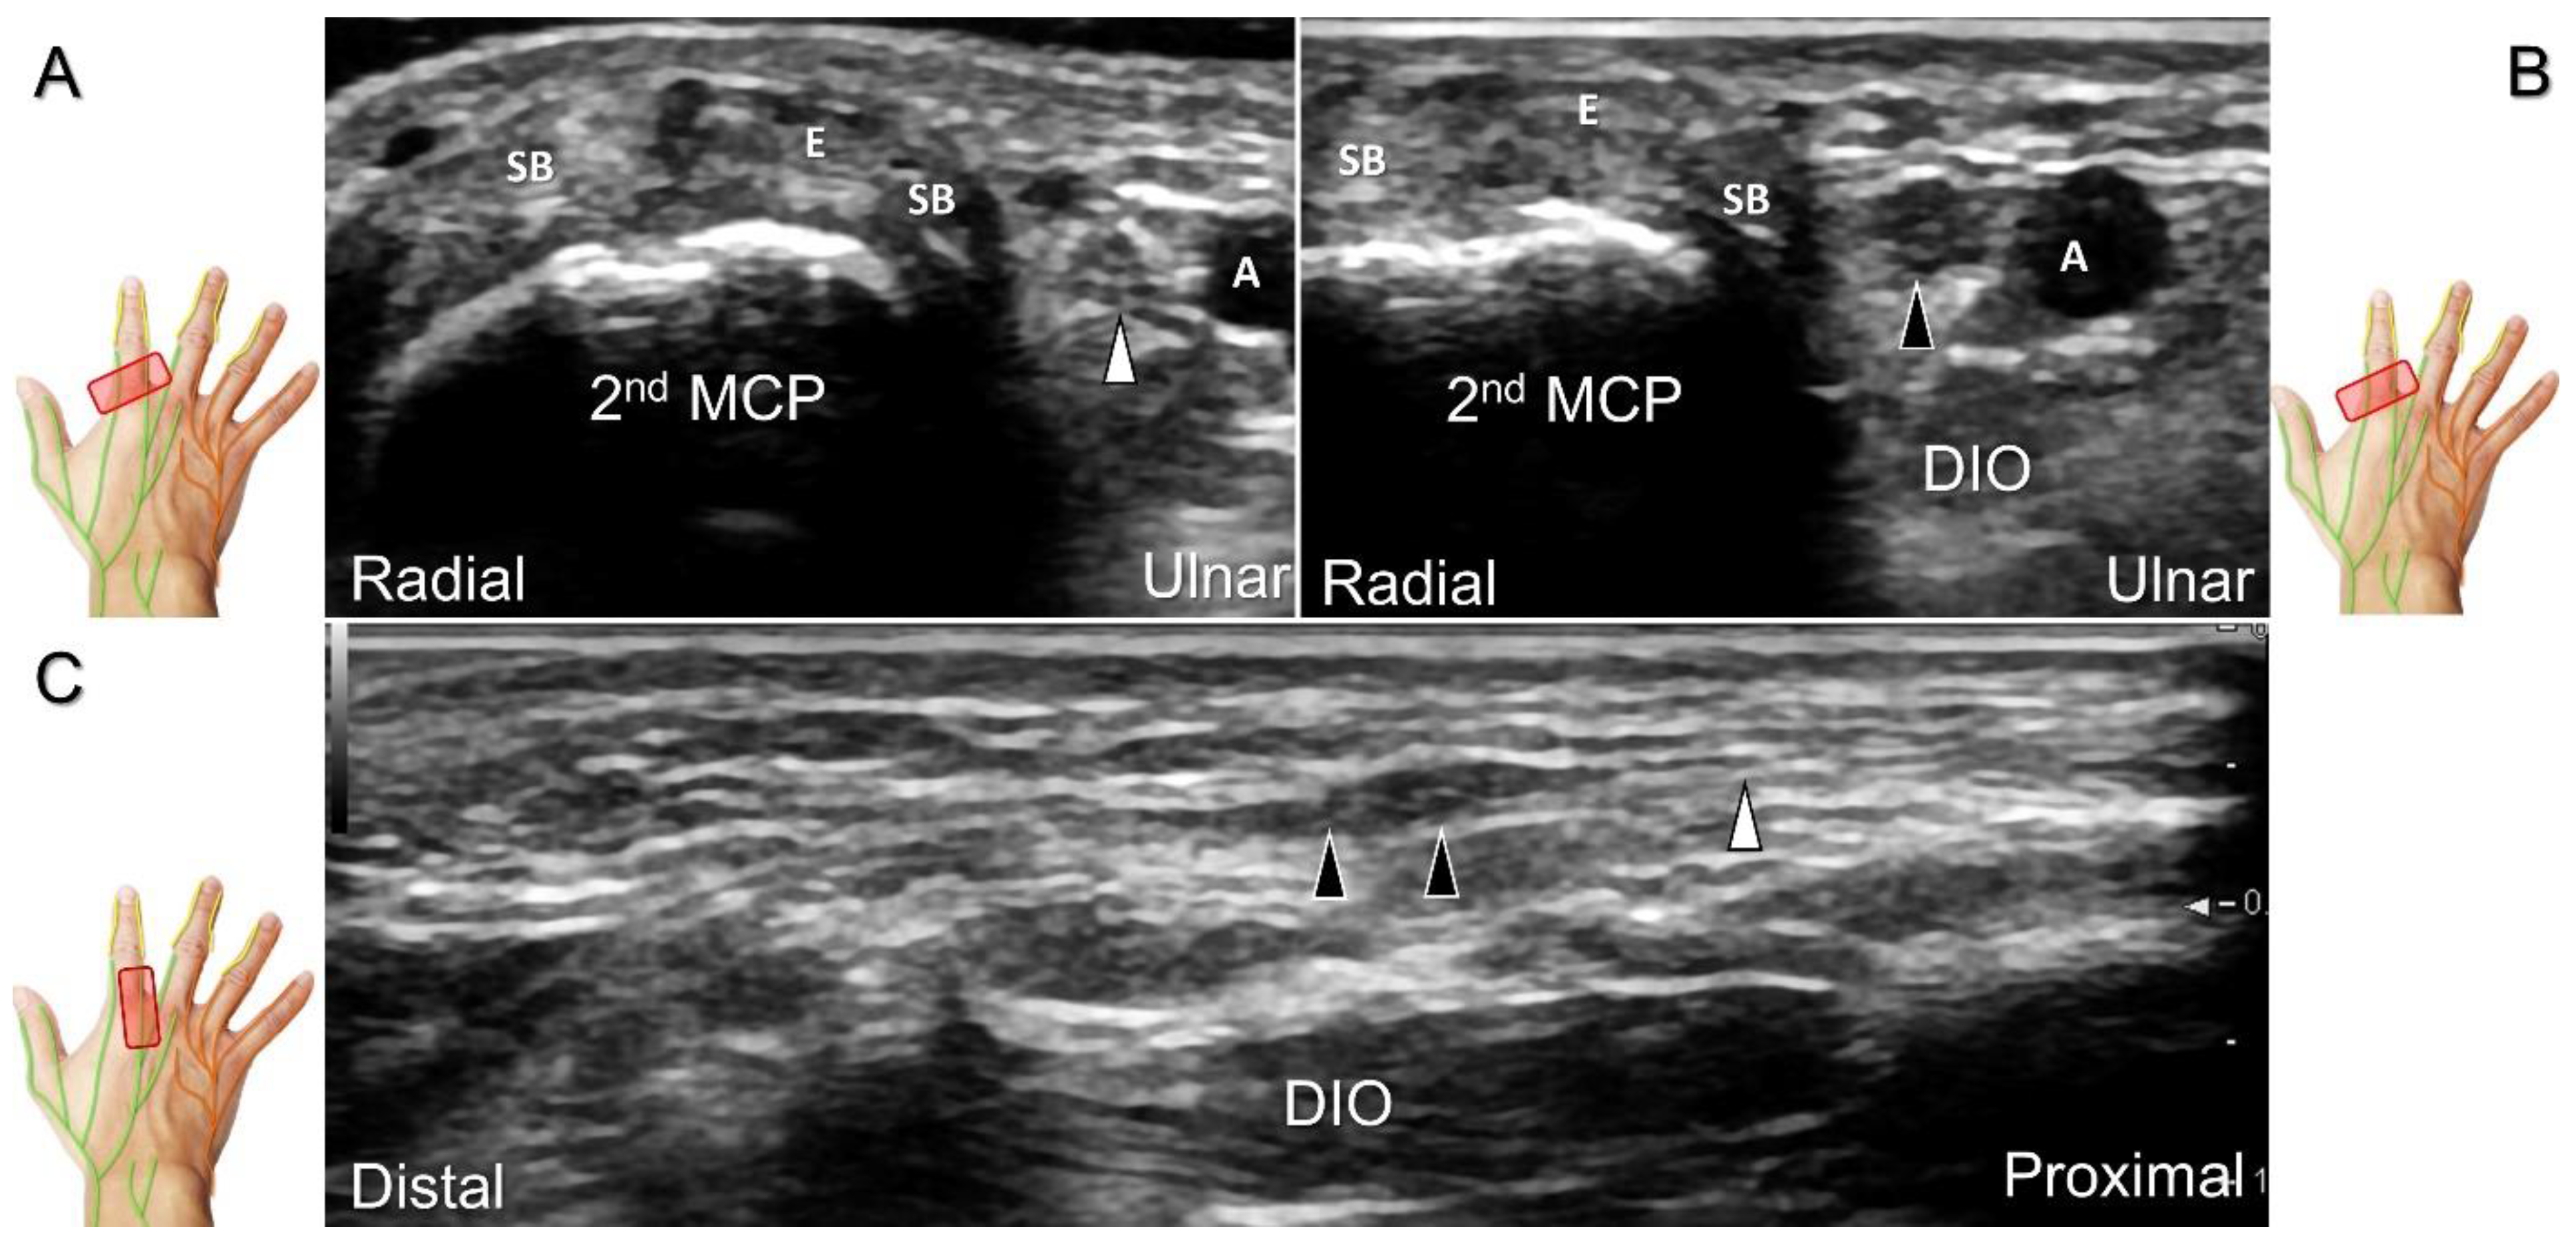

Scanning Technique

The transducer is positioned on the axial plane of the dorsal metacarpal joint in the target digit. The dorsal proper digital nerves can be found on either side of the sagittal band (Figure 33A). The transducer is moved proximally and the dorsal common digital nerves can be observed superficial to the extensor (usually the extensor digitorum proprius) tendons (Figure 33B). By returning to the level of the sagittal band and moving the transducer distally, the dorsal proper digital nerves can be seen superficial to and alongside the central slip of the finger extensor tendon (Figure 33C). Alternatively, moving the transducer distally toward the proximal phalanx of the first to the radial aspect of the fourth phalanx allows observation of the nerve fascicles of the palmar proper digital nerve originating from the median nerve (Figure 33D).

Clinical Implication

Injuries to the dorsal common digital nerve typically occur in the workplace as a result of cutting or crushing. However, the nerve can also sustain damage due to various other factors such as fracture, ganglia, tenosynovitis, tumor (Figure 34), foreign objects, or boxing, which may cause contusion over the first knuckles (Figure 35).

US imaging may reveal a neuroma in cases where patients report chronic allodynia and/or tingling sensation in the affected digit (Figure 36). To perform hydrodissection, the in-plane approach can be utilized in the nerve’s short axis after identifying the extensor digitorum tendons and the dorsal metacarpal arteries (Figure 37).

Figure 33. Sonographic imaging of the dorsal common digital nerve on the metacarpal bone (A), toward the metacarpal head (B). Dorsal proper digital nerves on the proximal phalanx (C), and the terminal nerve originating from the palmar proper digital nerve on the distal phalanx of third finger (D). Arrowheads: dorsal common digital nerve; arrows: palmar proper digital nerve. MCP: metacarpal bone; SB: sagittal band; E: extensor tendon; Cs: central slip; PP: proximal phalanx; T: terminal band; DP: distal phalanx; DIO, dorsal interosseous muscle.

Figure 36. Sonographic imaging (short-axis view) for a neuroma of the dorsal common digital nerve, proximal site (A) and the site of the lesion (B). Long-axis imaging of the nerve/neuroma (C). White arrowhead: normal dorsal common digital nerve; black arrowheads: neuroma. SB: sagittal band; E: extensor tendon; MCP: metacarpal bone; DIO: dorsal interosseous muscle; A: artery.